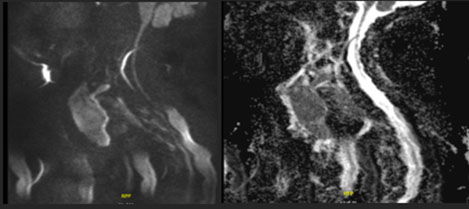

Fourteen years later, the patient presented to our institution with a palpable cervical mass. A total body CT revealed a non-enhancing diffusely enlarged hypodense thyroid gland without the presence of enlarged lymph nodes or other significant abnormalities (Figure 3). A magnetic resonance (MR) examination of the neck done one month later showed a rapid increase in size of the thyroid gland demonstrating diffuse enhancement postgadolinium administration and restricted diffusion. It showed to exert mass effect on the surrounding structures and significant narrowing of the airways. No pathological lymph nodes were seen (Figure 4, Figure 5, Figure 6). Because of the patient’s previous history of lymphoma and rapid growth of the thyroid gland, the possibility of extra-nodal thyroid lymphoma recurrence was raised, and a core needle biopsy of the thyroid gland was done and sent to pathology which confirmed the presence of diffuse large B-cell lymphoma within the thyroid gland.

Figure 6: Sagittal DWI and ADC MR images (2025) showing a diffusely enlarged thyroid gland demonstrating restricted diffusion.

Share Image: